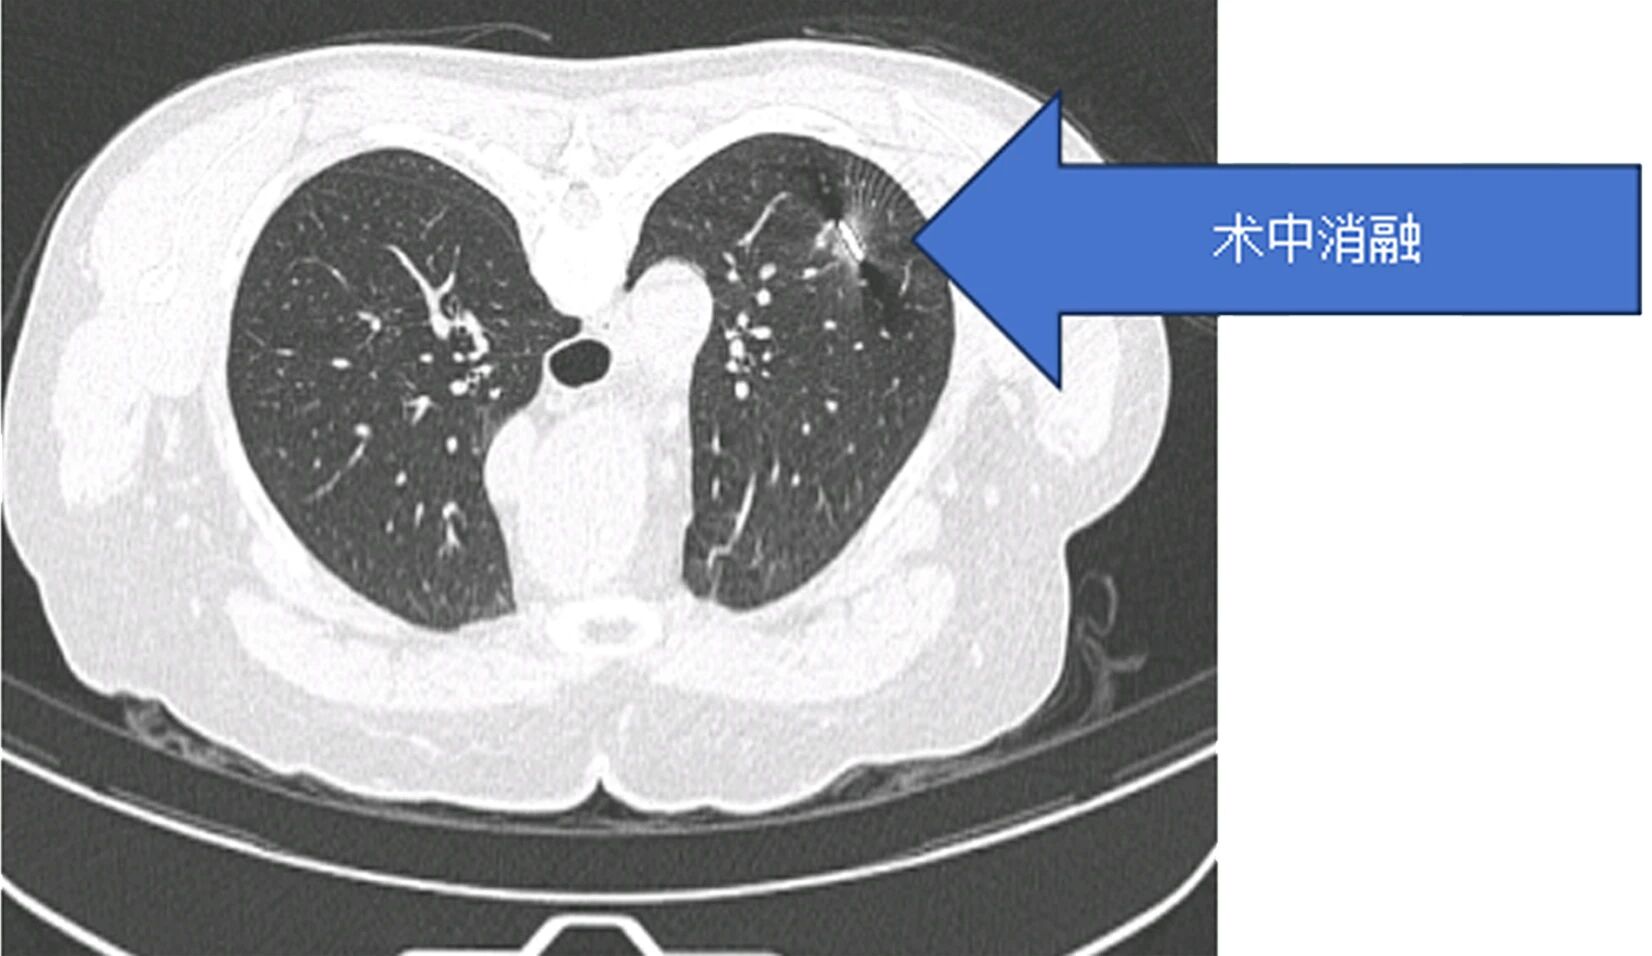

患者因肺结节就诊后,术前检查提示传统手术可能造成较大肺功能损伤,患者及家属因此产生明显焦虑情绪。胸外科团队综合评估病情后,决定采用微波消融技术施治。手术依托CT实时导航技术,将消融针精准送达结节部位,误差控制在3毫米以内,仅通过一个针孔创口完成操作,单次消融过程耗时5-10分钟,患者3天内出院,健康肺组织功能得以保留。